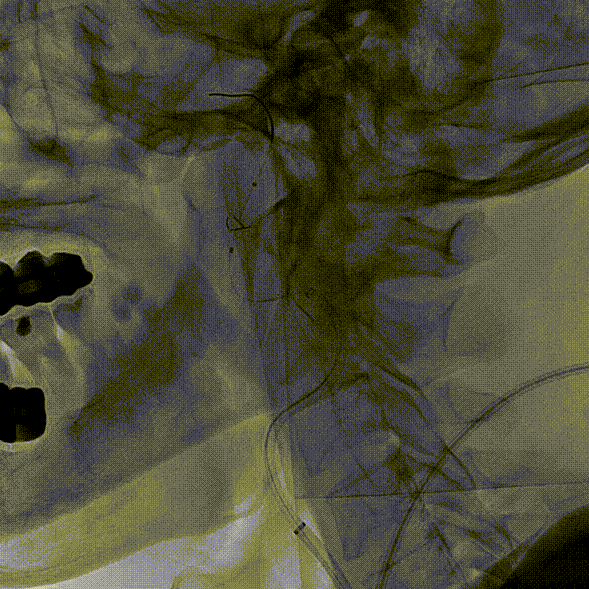

患者取平卧位置,常规消毒、铺巾和局麻右侧腹股沟下穿刺点后,穿刺置入5F动脉鞘,再以5F单弯行选择性脑动脉造影。造影示:II型主动脉弓,右侧颈内动脉C1段重度狭窄。

左侧颈动脉未见明显异常。

造影显示左侧椎动脉V1段中重度狭窄。